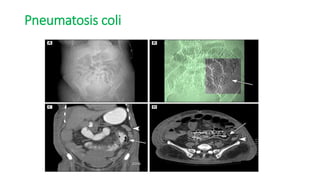

Pneumatosis coli

๏ƒ˜CT can show focal or segmental bowel wall thickening, intestinal pneumatosis,

bowel dilatation, or solid organ infarction.